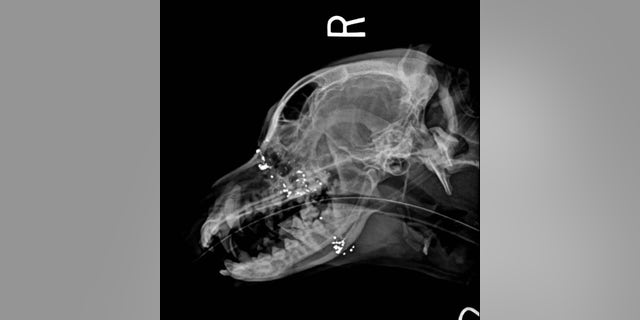

Veterinarians had cleaned the wound and took x-rays, and discovered it was a gunshot wound between his eyes.

“Arthur had been shot at an angle that miraculously missed his brain,” the PSPCA wrote. “The bullet left a hole in Arthur’s head & caused damage to his airway passages and mouth. He was covered in fleas, had ear infections and was anemic. But, he was alive.”

The organization said it remains hopeful that Arthur would make a full recovery, but there are still bullet fragments in his wound that may require specialty care.